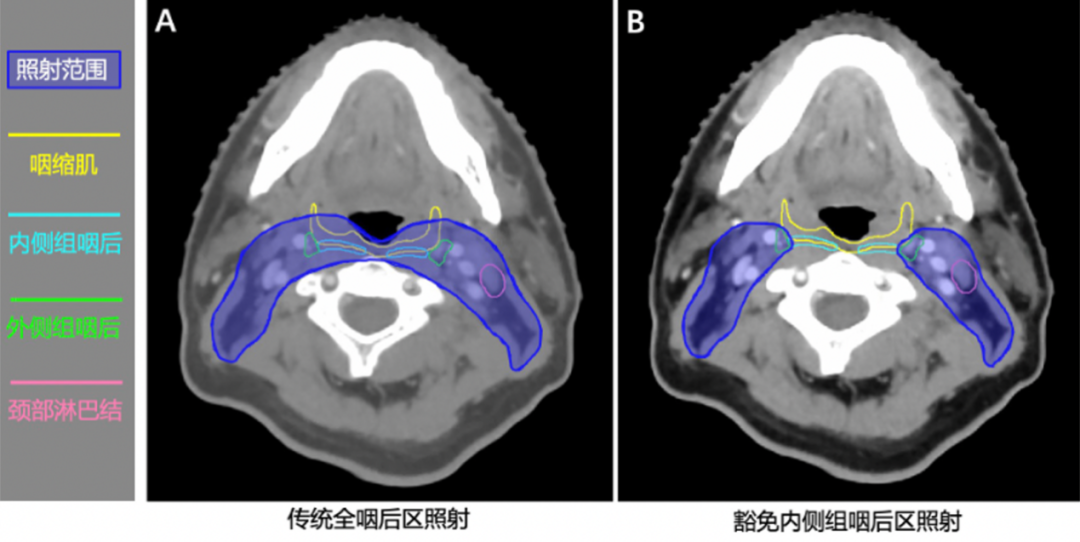

既往国内外指南推荐的全咽后淋巴结区预防照射是初诊无转移鼻咽癌的标准放疗方式,其照射范围过大,导致与之毗邻的吞咽相关结构(如咽缩肌、声门上喉等)受照剂量过高,吞咽困难发生率高达35.4%,甚至引发部分患者的误吸(66.9%)、吸入性肺炎(12%)、鼻饲或胃造瘘饮食(10%)等严重后果,严重影响患者的生活质量。前期研究团队基于高分辨率MRI的精准影像发现,尽管鼻咽癌咽后淋巴结转移发生率高,但主要集中于外侧组,内侧组极为少见(0.6%)。这一发现为缩小靶区范围提供了重要的理论依据。基于此,团队提出科学假设:豁免内侧组咽后区照射,可在不影响肿瘤局部控制率的前提下,降低咽缩肌的受照剂量,进而减少吞咽困难的发生。

为验证这一假设,团队首创了鼻咽癌“内侧组咽后区豁免放疗”的减毒新技术,并开展了一项568例的多中心、前瞻性、随机对照临床研究。3年结果显示,“内侧组咽后区豁免放疗”组的无局部复发生存率非劣于标准放疗组,并显著降低了吞咽困难的发生率、改善了生活质量。在此背景下,本研究旨在通过更长期的随访数据,进一步夯实生存证据,并深入揭示“内侧组咽后区豁免放疗”对吞咽功能保护的原理。

图1:内侧组咽后区豁免放疗新技术